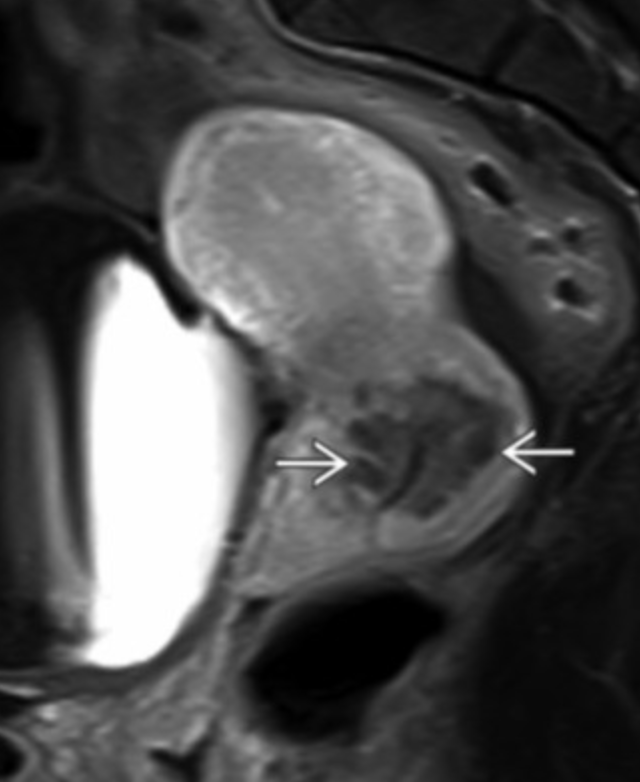

• Specific to MR

• Thick junctional zone with indistinct margins

• T2 bright foci in endometrial & myometrium (sometimes T1 bright too)

• This is how you differentiate it from a fibroid